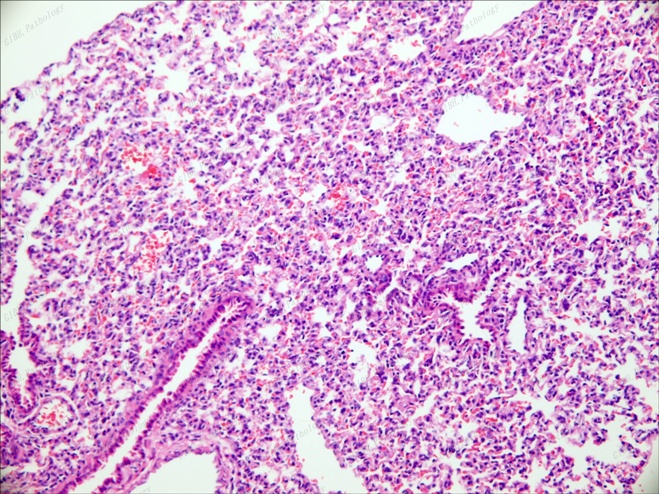

肺泡20